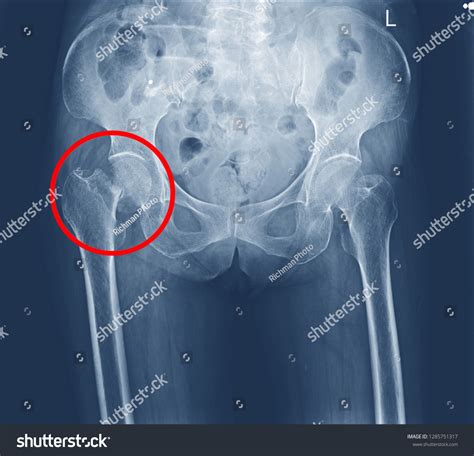

Fractures of the neck of femur are common, particularly in older adults and individuals with osteoporosis. These fractures can be classified into several types based on their location and pattern:

• Subcapital Fractures: Occur just below the femoral head.

Fractures of the neck of femur often result from falls or high-impact trauma. They can be particularly challenging to treat due to the limited blood supply to the femoral head, which can lead to complications such as avascular necrosis.

Avascular Necrosis

Avascular necrosis, also known as osteonecrosis, occurs when the blood supply to the femoral head is disrupted, leading to the death of bone tissue. This condition can be caused by various factors, including trauma, alcoholism, and certain medications. Avascular necrosis can result in severe pain and disability, and it often requires surgical intervention.